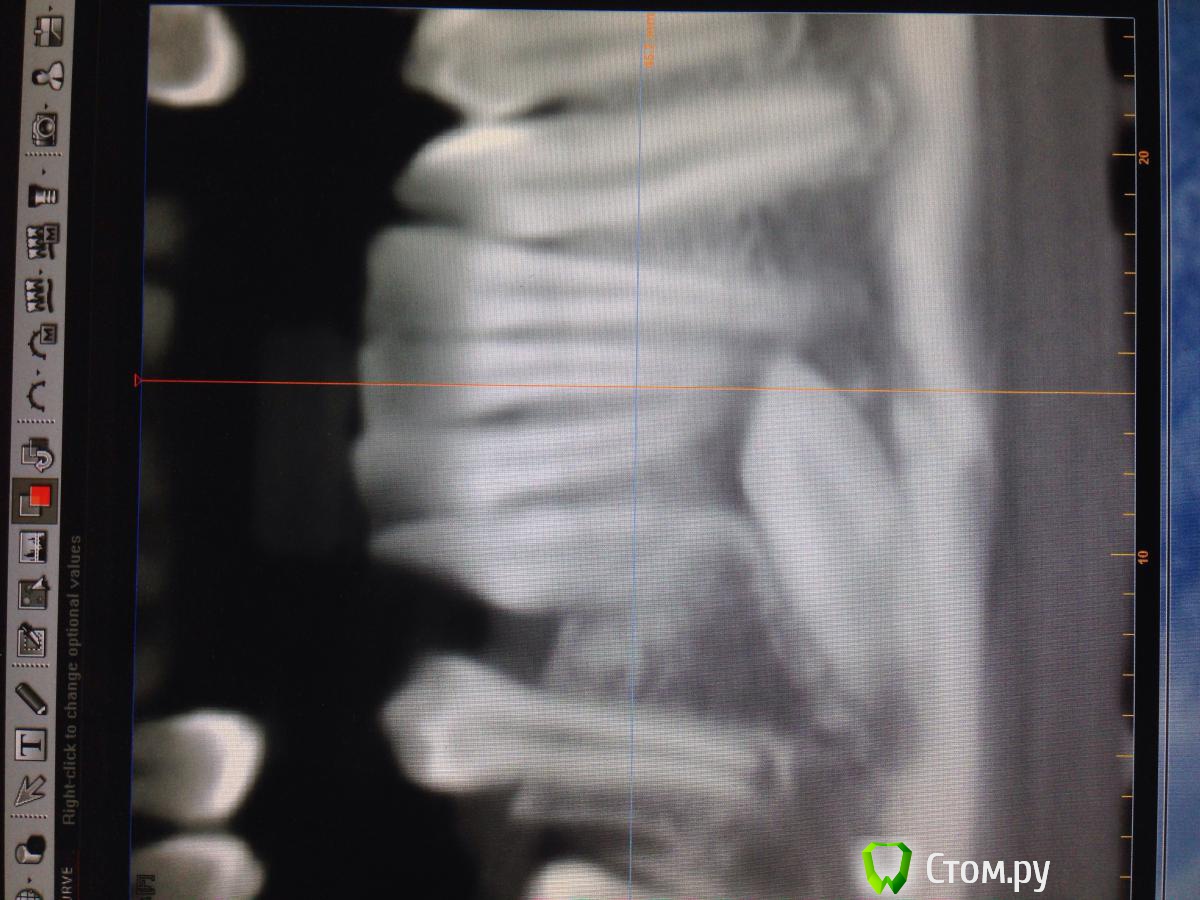

Opimar Опубликовано 29 ноября, 2013 Поделиться Опубликовано 29 ноября, 2013 Прошу совета по тактике лечения. Ортодонты привели пациента, 43 надо удалять. Впринципе ничего такого я не вижу, но все-таки как грамотно поступить взяться амбулаторно или направить в стационар. План лечения: Внутрибороздковый пошире с отслойкой передней поверхности подбородка ну и бор машиной фрагментировать зуб и удалить, либо без фрагментации если так пойдет. Швы, антибиотики, холод. Ну и предупредить о возможном онемении и травме резцов. Ссылка на комментарий